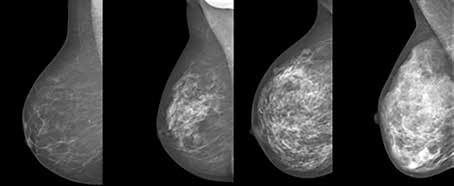

ur kvinnors bröst ser ut varierar mycket mellan olika individer. Bröst som blir vita på en röntgenbild innehåller mycket bröstkörtlar och stödjevävnad och kallas för täta bröst. I ett bröst som blir grått som på bilden är bröstkörtlarna tillbakabildade och det innehåller mer fettväv. Inför menopaus minskar östrogenproduktionen och bröstkörtelvävnaden ersätts av fett. Många kvinnor behåller dock täta bröst även efter fertil ålder. Tar man hormonersättning till exempel östrogen i samband med menopaus behåller man mer av sin brösttäthet. Det finns en ökad risk att få bröstcancer om man har täta bröst och tumörerna är dessutom svårare att se på mammografi. Man kan mäta brösttäthet visuellt genom att en röntgenläkare tittar på bilderna eller digitalt genom att mäta vita och svarta pixlar direkt i röntgenbilden. Förändringar i ett bröst tex tumörvävnad blir också vita på röntgenbilder. Det är därför svårt att hitta förändringar i ett bröst med mycket körtlar där det redan finns vävnad som blir vit på bilden.

Fyra bröst med olika täthet i körtelvävnaden.